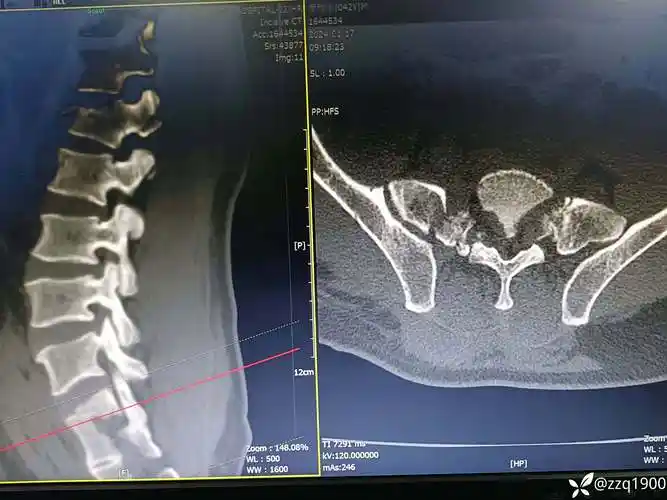

病例分享腰椎骶骨骨折如何处理